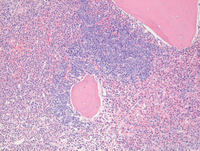

Bone core biopsy-higher power examination

On closer examination, the large sheet-like clusters of mononuclear cells are immature early erythroid precursors (proerythroblasts) forming tight clusters while the adjacent interstitial areas demonstrate prominent granulocytic proliferation including several eosinophils. Megakaryocytes are unremarkable (not shown).

Bone core biopsy Glycophorin-C stain

Additional Glycophorin-C stain highlights the clusters of cells confirming erythroid lineage. Although not shown here, CD34 stain did not show any increase in blasts. CD117 immunostain demonstrated weak staining in the erythroid precursors and in addition highlighted increased numbers of dispersed mast cells throughout the biopsy although large tight mast cell clusters were not present.